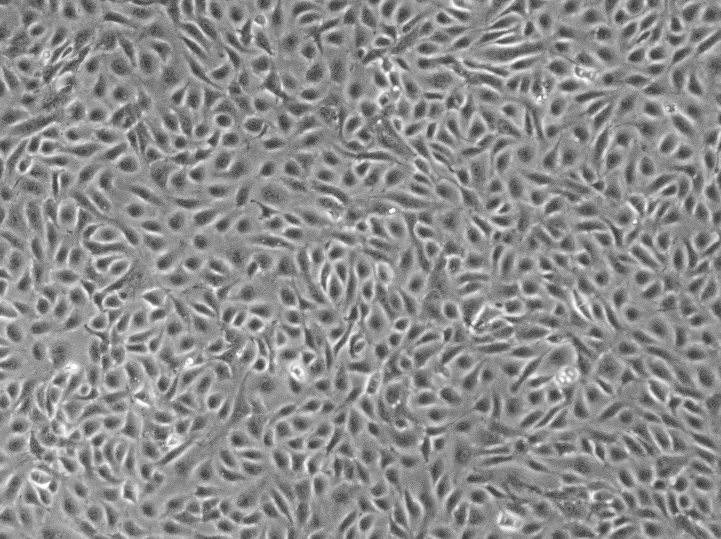

形态:上皮细胞样

背景资料:该细胞来源于一名63岁白人男性的移行细胞乳头状瘤,可作为转染宿主。